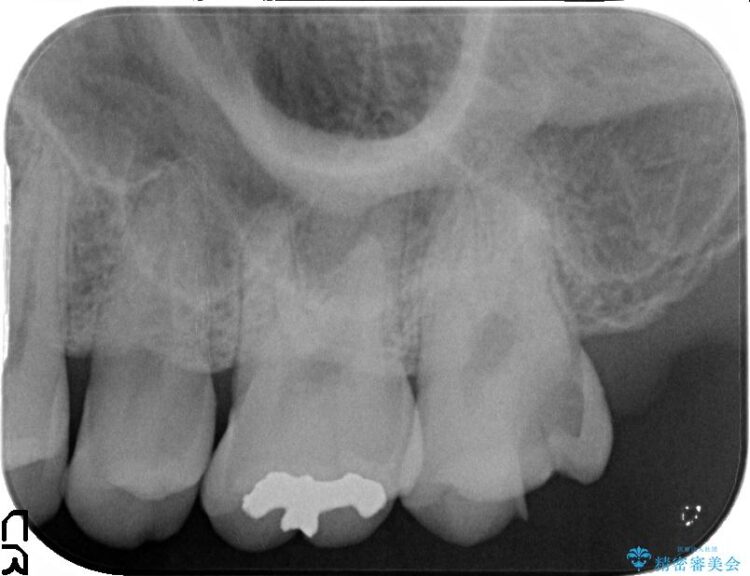

上顎左の一番奥の歯が深い虫歯になって脆くなり、更にその状態に強く噛みしめたわけではない通常の咬合力が加わったことで歯が欠けてしまっていました。

今回は一番奥の歯という位置と、噛み合わせ、清掃状態を加味して適合の高く長持ちするゴールドインレーにて治療することとしました。